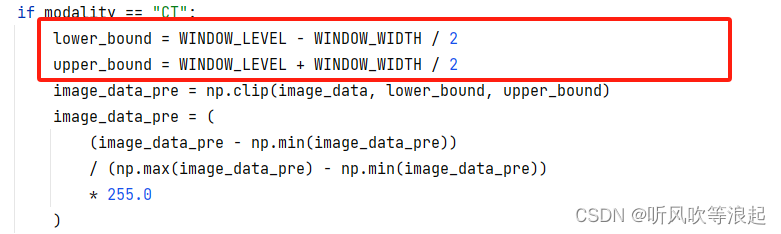

5.3.2 窗口宽度、窗口高度

学术叫法是 windowing 方法,专门处理医学图像这种灰度范围大的预处理方法

之前本人也写过,参考:医学图像处理的windowing 方法_医学图像常用windowing和histogram equalization-CSDN博客

其实说白了就是数字图像处理中的灰度拉伸,例如直方图均衡化啊、grammar变换啊、log变换啊等等都可以,只不过窗口化方法最好而已

就如下面图像,原始的医学图像可能是最右面的图像,经过windowing方法,变成最左边的,当然分割变得容易喽